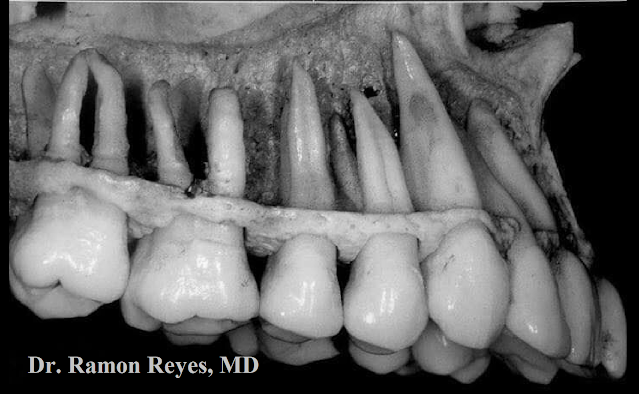

#ImagenDelDíaMSP | Cráneo de un niño mudando sus dientes de leche a dientes permanentes.